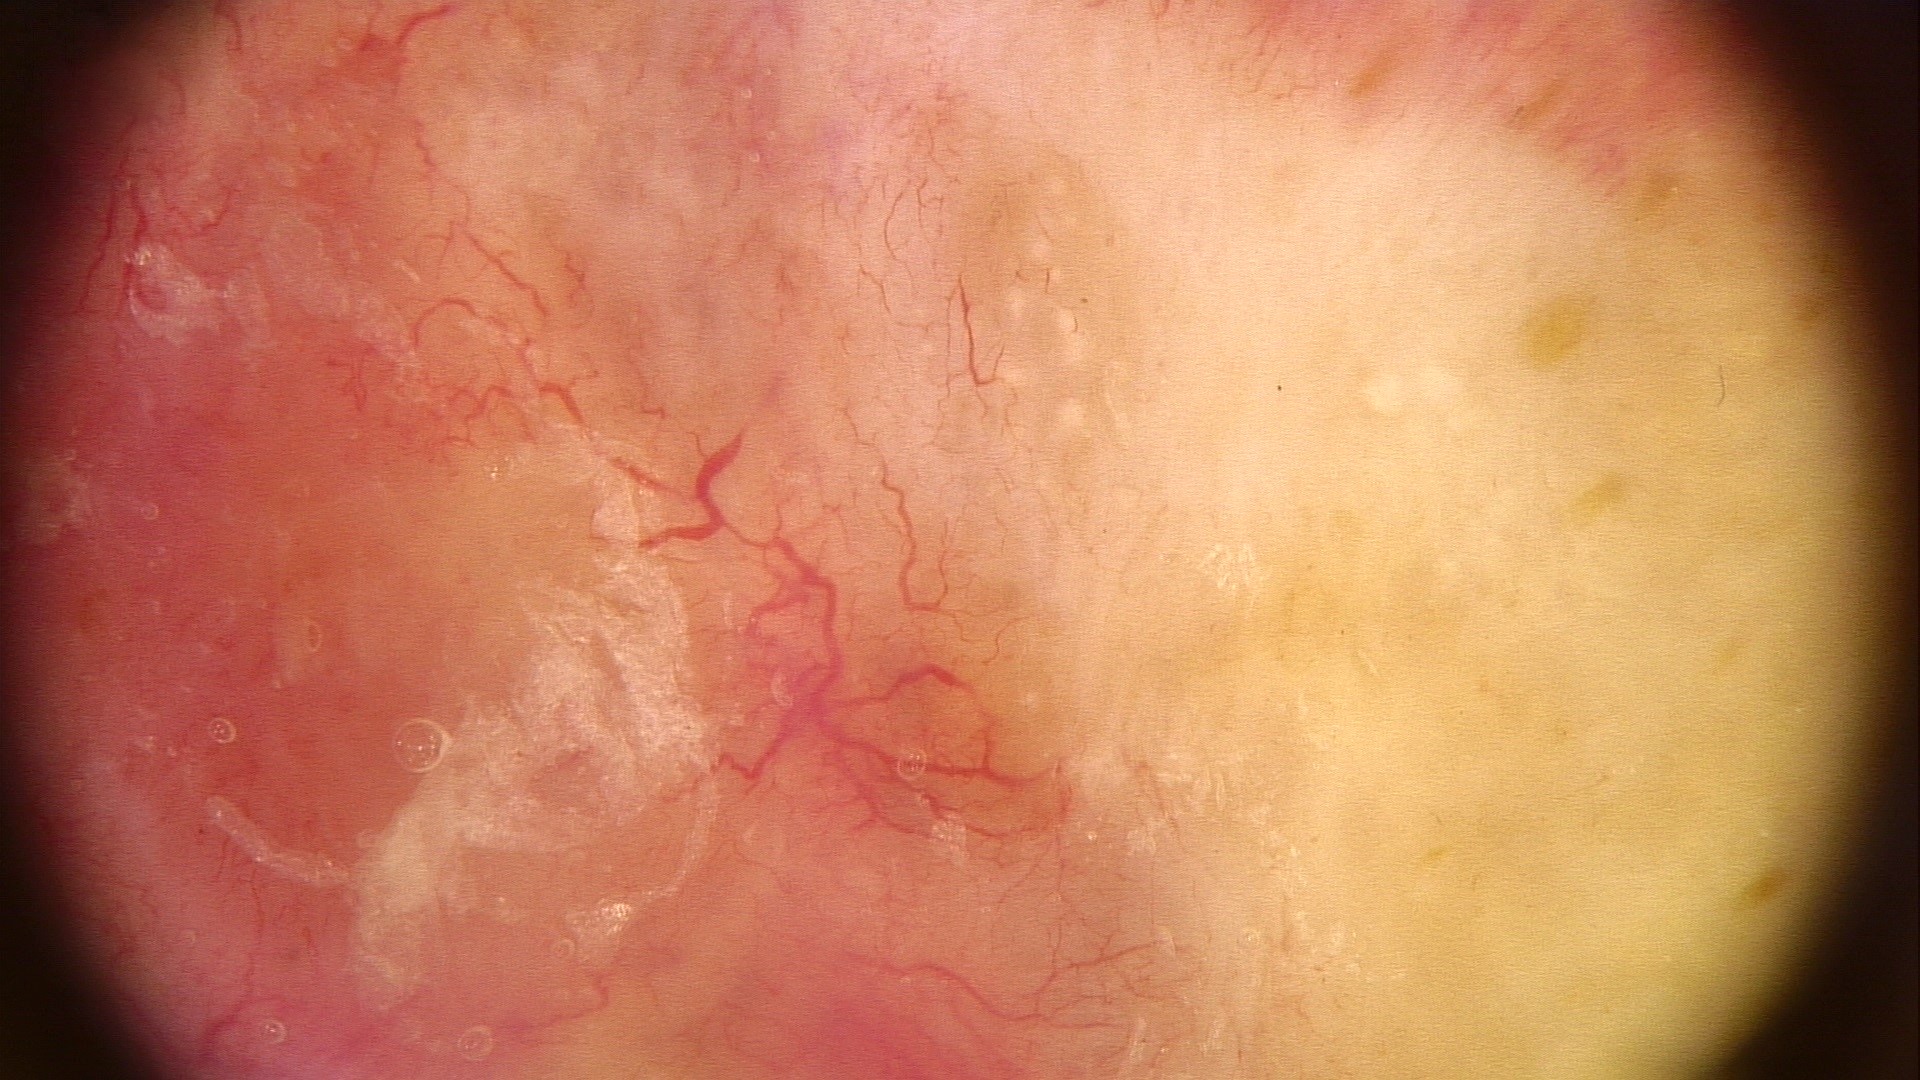

Clinical features

- Nodular variant usually presents as a pearly pink or flesh colored papule or nodule with arborizing and branching vessels (Br J Dermatol 2002;147:41)

- Superficial variant presents with scaly macules, patches or plaques with an erythematous surface

Clinical images